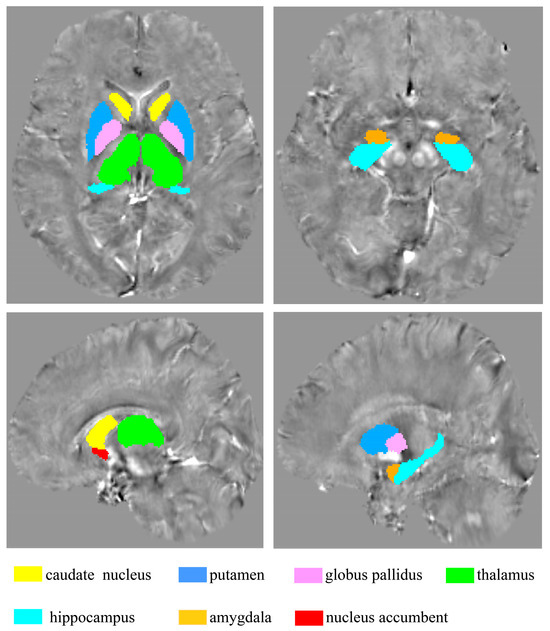

The ROI-based comparison of iron concentration in the brain between MDD and HC groups was conducted using fourteen ROIs delineated by the HOSubCort Atlas, as illustrated in Figure 5. This approach served to validate the results of the “MCCA+jICA” analysis.

Figure 5.

Fourteen ROIs were obtained according to the HOSubCort Atlas.